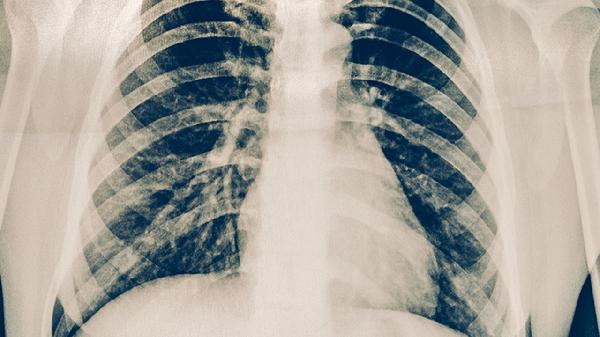

康复期间建议睡硬板床保持脊柱中立位,使用三角枕减轻翻身时的疼痛。饮食上多食用乳制品、深绿色蔬菜及海产品,避免辛辣刺激食物。戒烟戒酒以保证组织供氧,每日晒太阳20分钟促进维生素D合成。疼痛完全消失前禁止提重物及剧烈运动,定期复查X线观察骨痂生长情况。出现持续发热或呼吸困难需立即就医。